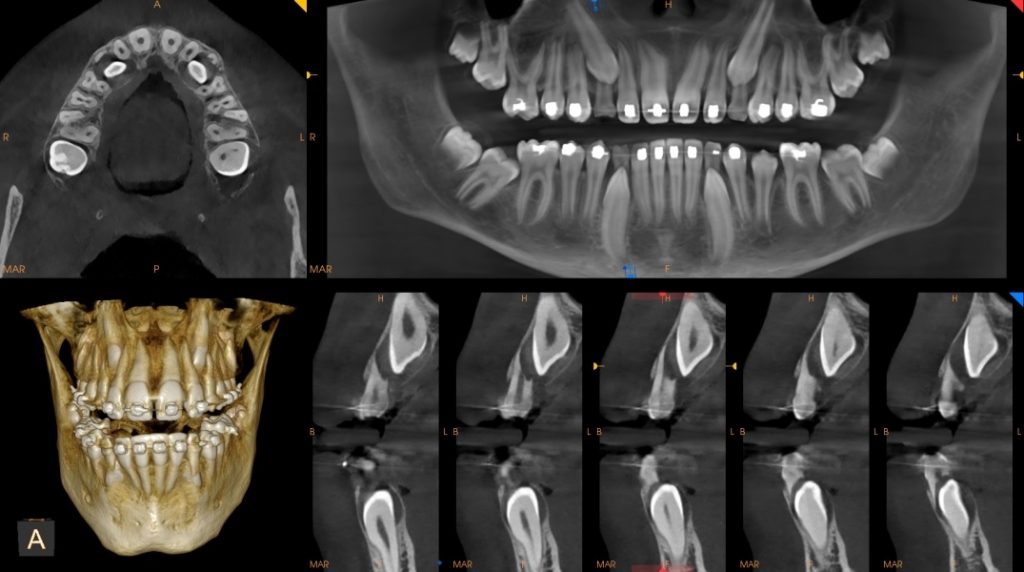

Le radiografie tradizionali, quelle bidimensionali, offrono una visione piatta delle strutture dentali. Sono utili, ma limitate. Le radiografie 3D, conosciute anche come TAC dentali o Cone Beam, permettono invece di visualizzare denti, ossa e tessuti da ogni angolazione.

È come passare da una fotografia a una vera e propria esplorazione in profondità. Il dentista può analizzare ogni strato, individuare problemi nascosti e pianificare interventi con una precisione millimetrica.

Le applicazioni sono numerose e riguardano diversi ambiti dell’odontoiatria. Nella chirurgia implantare, per esempio, la radiografia 3D consente di valutare con esattezza la quantità e la qualità dell’osso disponibile, riducendo i rischi e migliorando il risultato finale.

Anche nei casi di denti inclusi, infezioni profonde o problematiche articolari, questa tecnologia permette di individuare dettagli che altrimenti potrebbero sfuggire. Il risultato è una diagnosi più accurata e un piano di trattamento più sicuro.

Uno degli aspetti più affascinanti dell’odontoiatria digitale è l’integrazione tra strumenti diversi. Le radiografie 3D e lo scanner intraorale non lavorano separatamente, ma dialogano tra loro. I dati raccolti vengono combinati in software avanzati che permettono di creare un modello completo del paziente. Questo modello diventa la base per pianificare interventi, simulare risultati e realizzare dispositivi su misura.

In implantologia, ad esempio, è possibile progettare virtualmente l’inserimento di un impianto, valutandone posizione e inclinazione prima ancora di iniziare l’intervento. Questo approccio riduce i margini di errore e aumenta la prevedibilità del risultato.